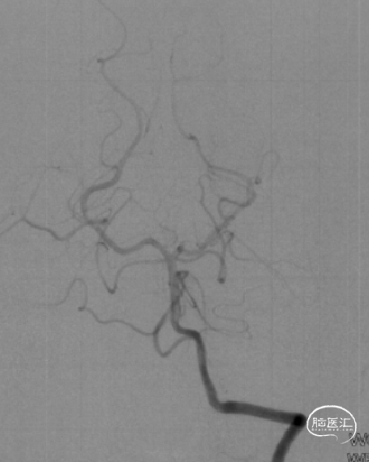

选用赛诺神畅 3.5-20mm COMETIU™自膨式颅内药物涂层支架系统通过病变并缓慢释放,释放后造影,支架定位准确,完全覆盖病变,成形效果好。

撤出导管导丝后造影,可见靶血管支架贴壁良好,前向血流通畅稳定。

术后行Dyna-CT未见异常,支架定位准确,贴壁良好。

再次造影观察,确认手术成功,结束手术。

2022-07-27 COMETIU™自膨式颅内药物涂层支架 3.5-20mm (正位)

2022-07-27 COMETIU™自膨式颅内药物涂层支架 3.5-20mm (侧位)